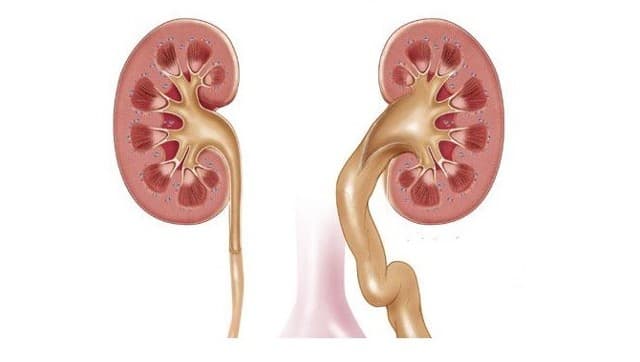

Рефлюксирующий мегауретер: Визуализация и медицинские изображения

Раздел: Фотопуть к знанию